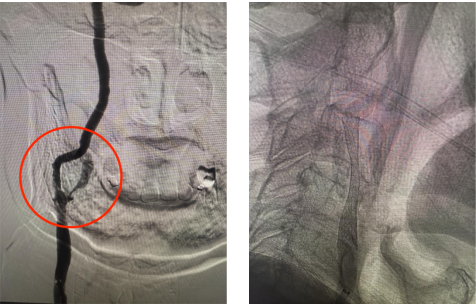

手术过程中,血管介入科团队以毫米级精度开展穿刺、置鞘、导引导管到位等步骤,精准地将微导丝穿过狭窄血管段,随后放置远端保护装置,如同为大脑血管筑牢“安全屏障”,有效预防术中斑块脱落引发栓塞。紧接着,选用合适规格的预扩张球囊对狭窄部位进行轻柔扩张,为支架植入开辟通路,随后将一枚自膨式支架精准送达狭窄段,缓慢释放并确认支架完全展开、贴壁良好。整个手术历时约60分钟,患者术后造影显示,患者颈内动脉狭窄部位血流完全恢复通畅,无残余狭窄,手术达到了团队预期的效果。

上图为手术过后血管狭窄明显改善,症状改善